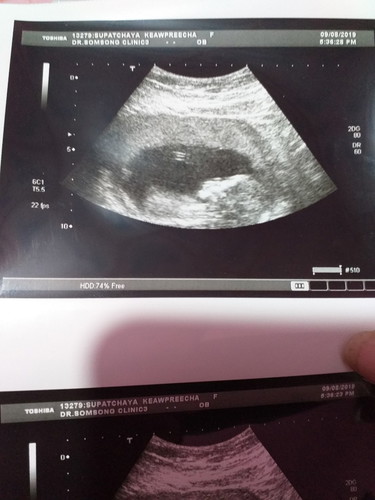

ไปหาหมออัลตร้าซาวที่คลีนิคมาหมอบอกแข็งแรงดีไม่มีไรต้องกังวลแถมอีกอย่างเห็นเพศหญิง95%จร่าาสมจัยแม่จร่าาา